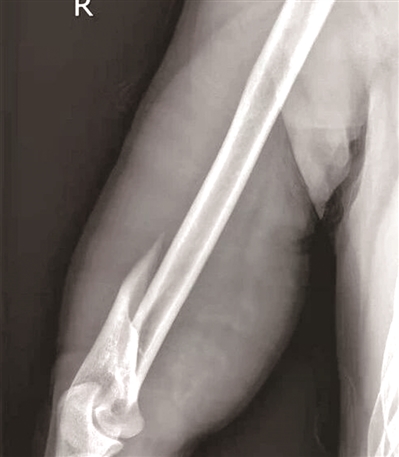

小马肱骨呈螺旋形骨折

2021年3月的一天,30岁的小马在街边烧烤摊和朋友小聚。酒过三巡和朋友“掰手腕”比力气,小马猛然发力,忽然“咔嚓”一声右臂剧痛,动弹不得。送到杭州市一医院急诊,X光片显示“肱骨干断裂”,断掉的肱骨好似麻花一样,呈现螺旋形状。

浙江省中医院骨伤科医生李飞说,掰手腕时,手臂肌肉会瞬间爆发出强大的收缩力,这股力量沿着上臂骨骼(肱骨)传导,肱骨中下段就像一根筷子最容易被掰断的位置,非常不耐“扭转”和“剪切”。当姿势不当,强大的力量持续对抗时,肱骨就可能像被硬生生掰断的树枝一样,发生螺旋形骨折。